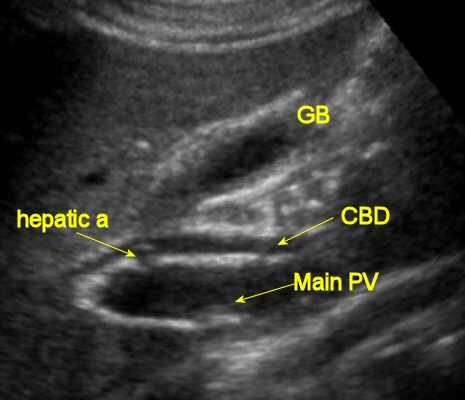

Normal ultrasound view of the CBD and portal vein

The normal CBD width

< 6 mm up to age 60, then an additional 1 mm per decade thereafter

ie, 7 mm for 70, 8 mm for 80, and so on